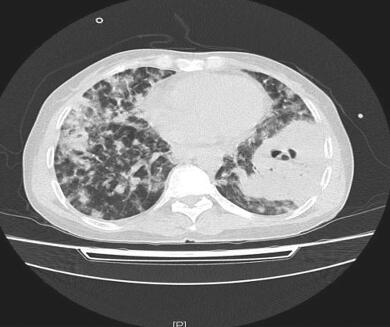

抗生素改用美罗培南、复方磺胺甲噁唑片抗感染,并给予丙种球蛋白静脉滴注,3天后患者体温逐渐下降至正常。血培养未再发现病原菌,继续使用抗生素21天后,患者病情稳定,症状明显好转,复查肺部CT病灶(图2)较前有吸收,给予出院,继续口服复方磺胺甲噁唑片、阿莫西林/克拉维酸钾,并门诊随访,2014年12月1日复查肺部CT(图3),病灶较前明显吸收。

图2 2014年7月31日胸部HRCT

双肺弥漫性斑片影较前吸收,左下肺空洞影,壁厚